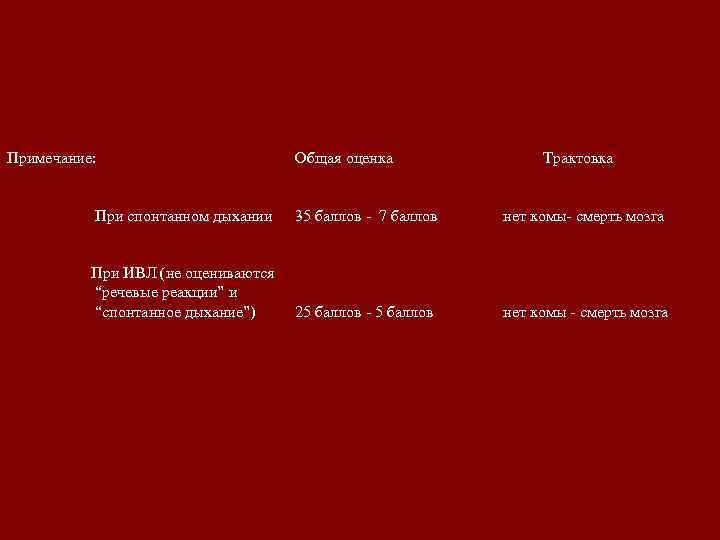

Примечание: Общая оценка Трактовка При спонтанном дыхании 35 баллов - 7 баллов нет комы- смерть мозга При ИВЛ (не оцениваются “речевые реакции” и “спонтанное дыхание”) 25 баллов - 5 баллов нет комы - смерть мозга

Примечание: Общая оценка Трактовка При спонтанном дыхании 35 баллов - 7 баллов нет комы- смерть мозга При ИВЛ (не оцениваются “речевые реакции” и “спонтанное дыхание”) 25 баллов - 5 баллов нет комы - смерть мозга